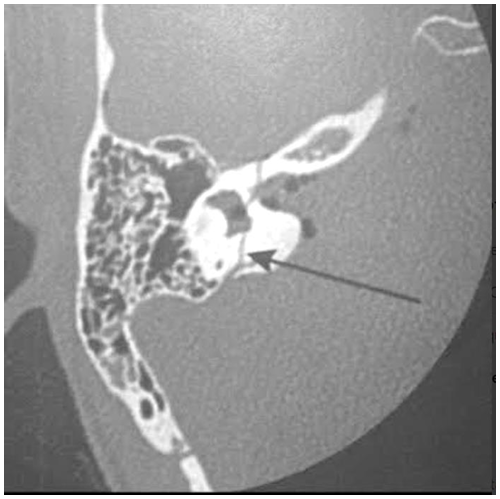

Analise o seguinte corte de tomografia computadorizada de mastoide e assinale a alternativa correta.